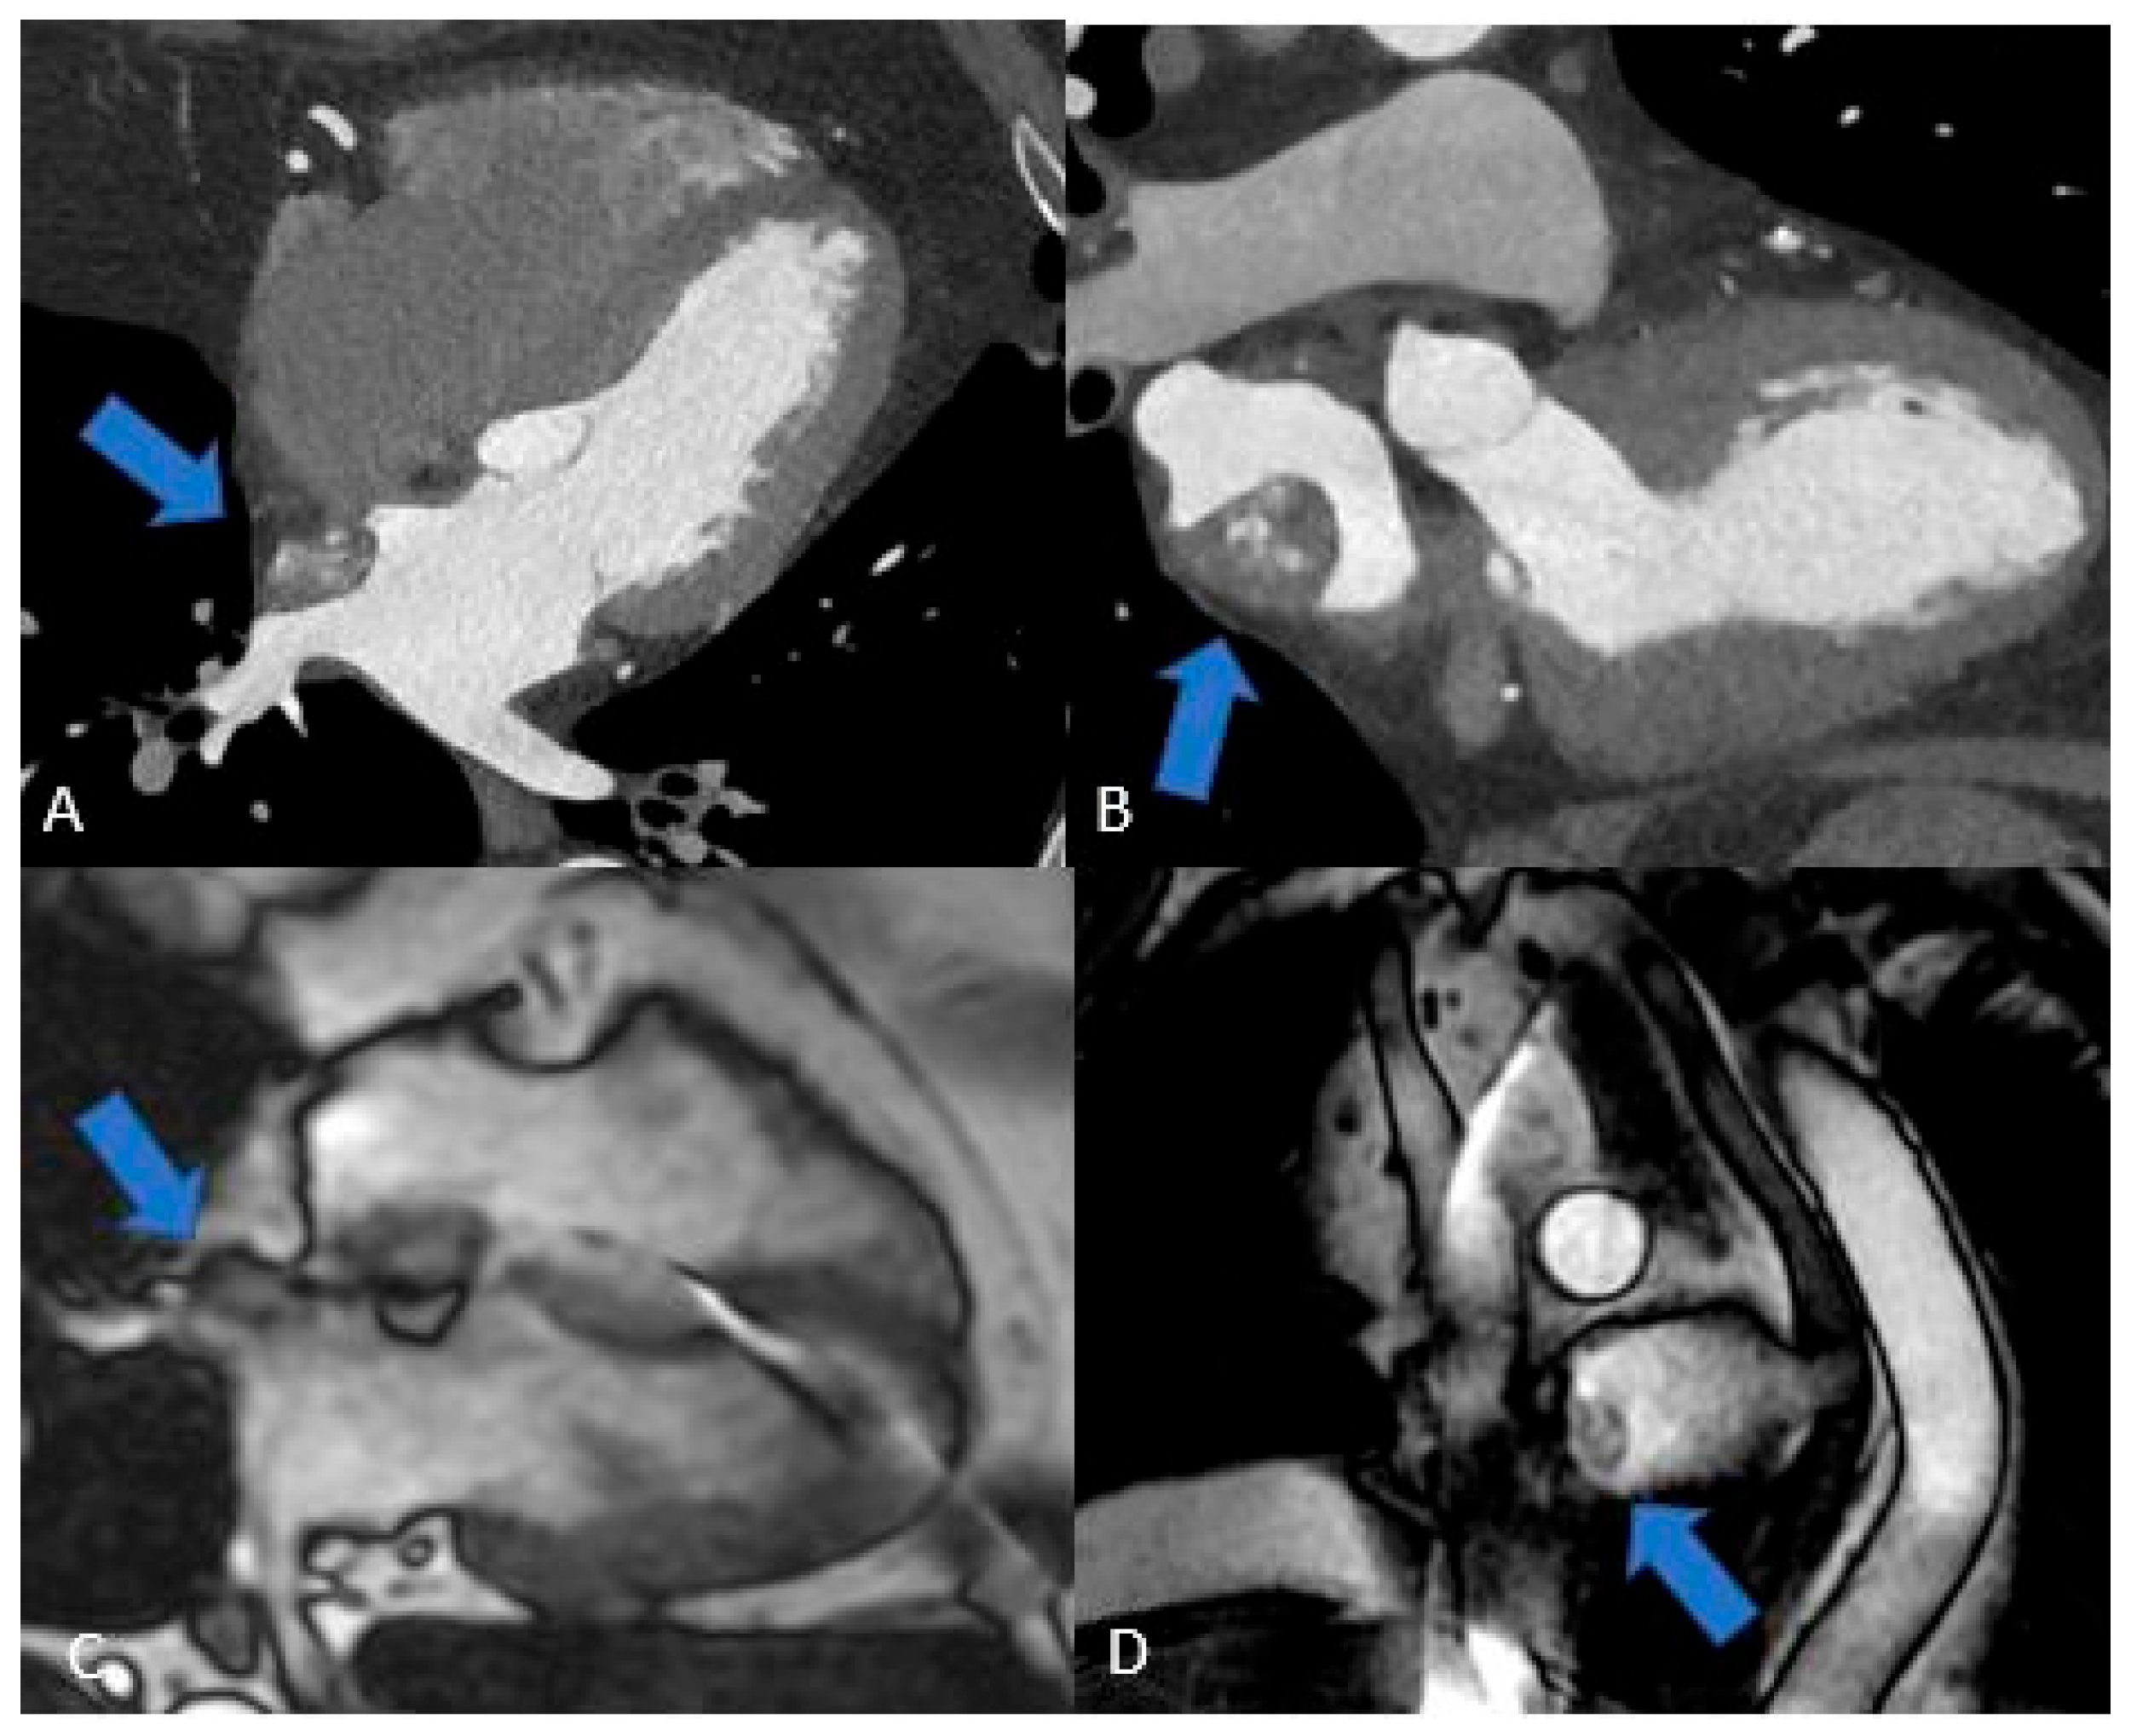

3.2. Pericardial Cysts

A pericardial cyst (Figure 4) is a congenital benign structure typically found in the right pericardiophrenic angle. It is usually an incidental finding, often discovered during an X-ray, and is generally small and asymptomatic. However, if very large, it can compress adjacent structures, both mediastinal and pulmonary. The appearance is typical of a cyst: hypodense on CT, hypointense on T1-weighted MRI, hyperintense on T2-weighted MRI, and it shows no contrast enhancement [3,9,22].

Figure 4. Two Pericardial Cyst in different location: A (CT) and B (MRI), superior recess of the pericardium anterolaterally to pulmonary artery CT. C, D, E, (MRI) the cyst is located in the infero-lateral atrioventricular groove close to the esophagus and descending aorta. The cystic nature of the lesions (arrows) is evident, and their well-defined borders help differentiate them from solid masses, aiding in the accurate diagnosis.